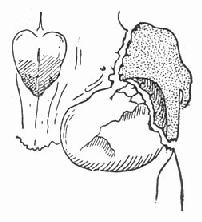

图88-14 颧骨及颧骨弓骨折